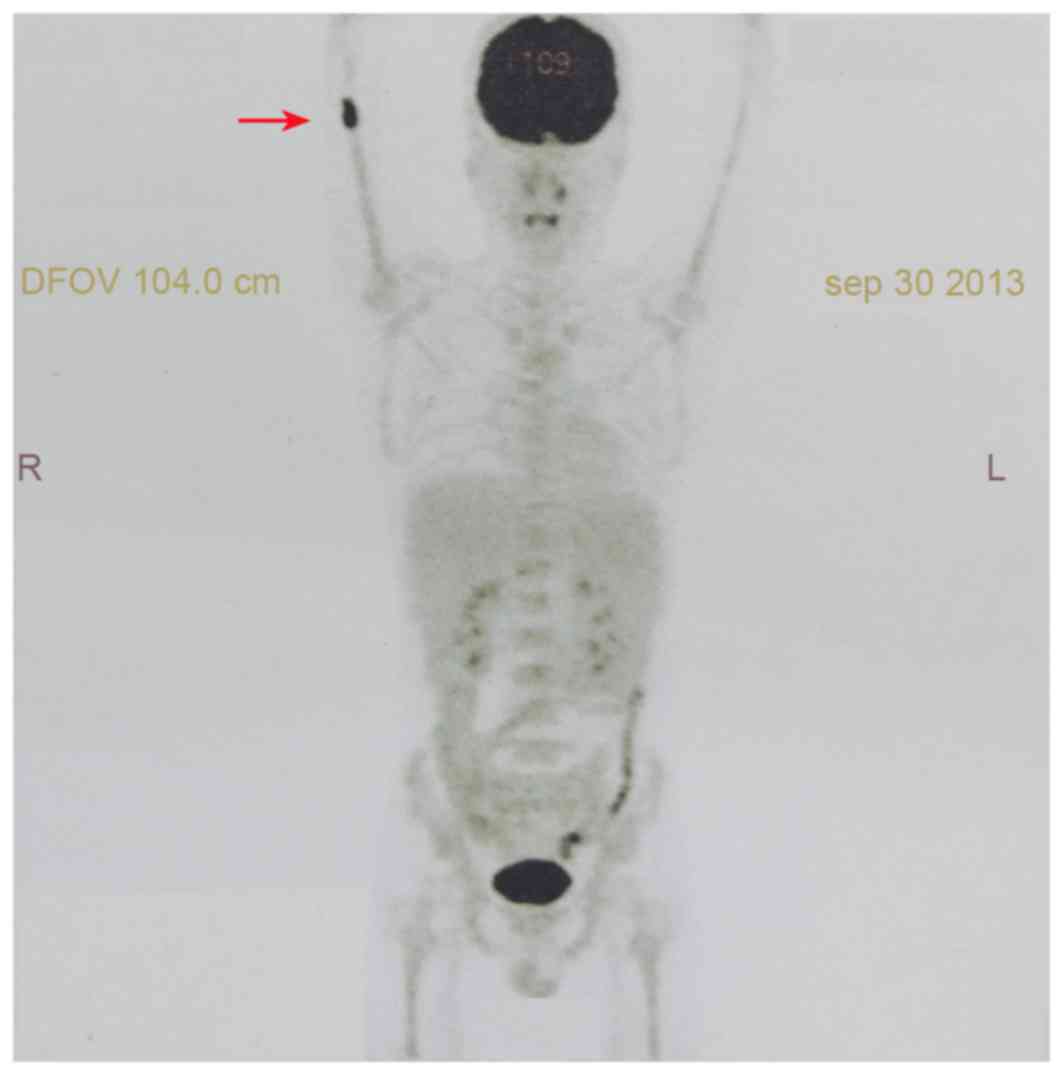

A 29-year-old male was admitted into Peking Union Medical College Hospital (Beijing, China) on October the 12th 2013, presenting with a 6-month history of pain in the right elbow and a 4-month history of fever. Previous examinations of the patient revealed pancytopenia, no tumor cell in bone marrow aspiration (BMA) and no abnormality in a computed tomography (CT) scan of the right upper limb. The patient had received antibiotics, but no improvement was observed. The patient also had a weight loss of ~4 kg. In addition, the patient reported a seafood allergy. Physical examination revealed a fever (37.8°C), a rapid heartbeat (112 beats/min) and a low blood pressure (89/56 mmHg). No superficial lymphadenopathy was determined, and the spleen could be touched under the ribs. A complete blood count (CBC) demonstrated decreased levels of white blood cells (WBC) (2.0×109 cells/l; normal range, 4.0–10.0×109 cells/l), neutrophils (1.2×109 cells/l; normal range, 2.0–7.5×109 cells/l), hemoglobin (8.6 g/dl; normal range, 12.0–16.0 g/dl) and platelets (36×109 cells/l; normal range, 100–300×109 cells/l). The activity of natural killer (NK) cells, determined as the activity to kill fluorescent plasmid transfected cells, was identified to be low (15.0%; normal range, 31.5–41.6%). Soluble cluster of differentiation (CD)25 was >44,000 pg/ml (normal, <6,400 pg/ml). An abdominopelvic CT revealed splenomegaly (9.0×23.0 cm; normal, 4.0×12.0 cm). An 18F-fluorodeoxyglucose (FDG) positron emission tomography (PET) scan demonstrated an increased uptake of FDG in medullary space of the right distal humerus (maximum standardized uptake value, 9.3) without evidence of dissemination at other sites (Fig. 1). BMA, using Wright-Giemsa staining, revealed 4% lymphoma cells and phagocytes engulfing hemocytes (optical microscope; magnification, ×1,000) (Fig. 2). Bone marrow biopsy (BMB) was embedded with paraffin and stained with ready-to-use hematoxylin and eosin for between 30 and 40 min, and incubated between 24 and 28°C (optical microscope; magnification, ×100) (Fig. 3). The proportion of hematopoietic tissue in bone marrow increased and the BMB revealed scattered and focal CD20-positive cells. According to the results of BMB, B cell lymphoma involving bone marrow was not excluded. Gene rearrangement detection, using multiplex polymerase chain reaction (IGH PCR assay; Invivoscribe, San Diego, CA, USA), identified a rearrangement in immunoglobulin κ (Vk−Kde+INTR−Kde+). The bone marrow karyotype was 46, XY [20]. Flow cytometric (FCM) analysis revealed that CD45+CD19+ cells, which were potentially abnormal B lymphocytes, expressed human leukocyte antigen-antigen d related, CD5, CD11c, CD20, CD22, CD38, limited FCM-7 antigen, no κ- or λ-polyclone, and accounted for 0.5% of nuclear cells.

Figure 1.

An increased uptake of 18F-fluorodeoxyglucose as indicated by positron emission tomography examination. The red arrow indicates a standardized uptake value of 9.3 in the bone marrow cavity of the right distal humerus. DFOV, display field of view; R, right; L, left.